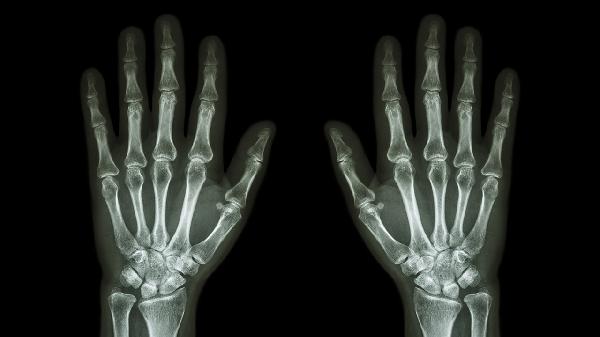

手指大拇指关节一按就疼可能与腱鞘炎、骨关节炎、外伤、痛风性关节炎、类风湿关节炎等因素有关。可通过热敷、药物治疗、制动休息、物理治疗、手术松解等方式缓解。

关节软骨退行性变会引发骨质增生和关节间隙狭窄。疼痛在负重时加重,可能伴随关节膨大变形。早期可口服硫酸氨基葡萄糖胶囊修复软骨,关节腔注射玻璃酸钠注射液润滑关节。严重畸形需行关节成形术。

撞击或扭伤可能造成关节囊损伤、韧带撕裂或微小骨折。局部可见淤青肿胀,活动受限。急性期应冰敷止血,48小时后改用活血化瘀膏药如消痛贴膏。疑似骨折需石膏固定4-6周。